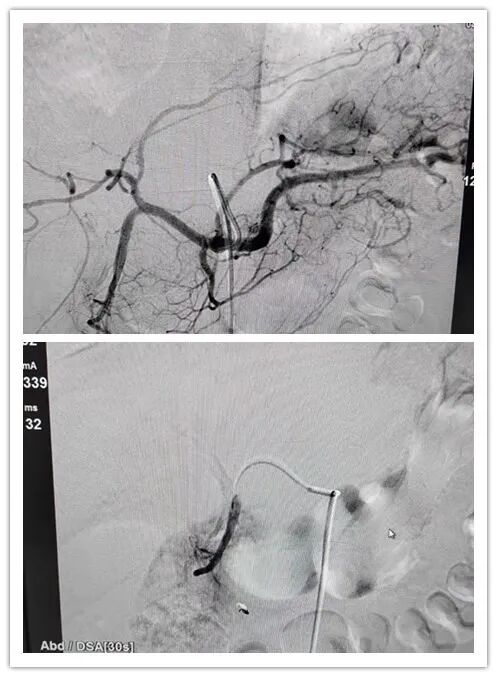

面对这样的情况,时间就是生命!修文百信医院会诊专家组立即制定

出完整的治疗方案:急诊行介入止血治疗。

经过整晚的不懈努力,抗争在死亡的边缘,该患者的血止住了!!患者生

命体征也逐渐平稳了下来,手术完美结束!

这就是介入治疗的魅力!不但挽救了一条鲜活的生命,对患者还没有

任何创伤,就是一个“小小的针眼”经过几天恢复也不会留下任何痕迹!

图片来源:介入肿瘤科